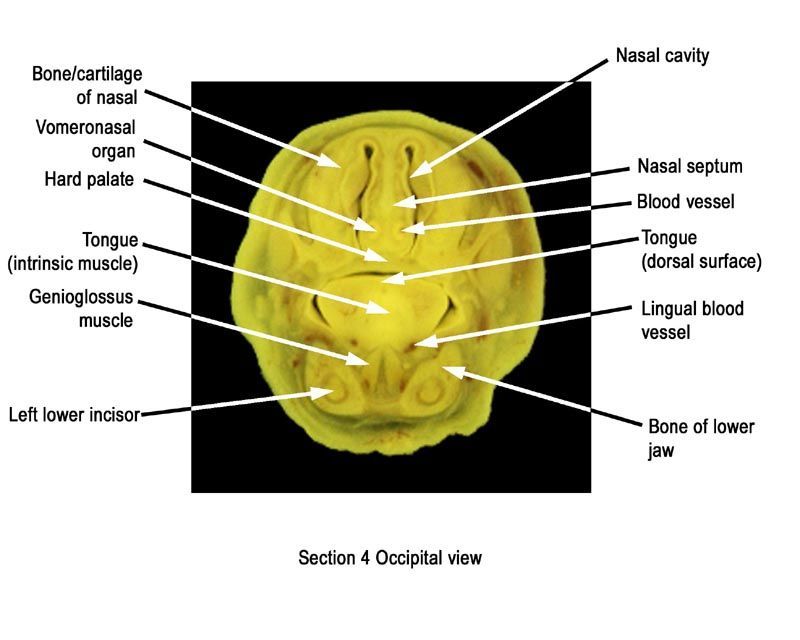

The images below show the normal appearance of Bouin's fluid fixed head sections in specimens at Day 21 of gestation (day mating observed = Day 0).

Learning objective: Compare the diagrams with your own specimens and identify all of the structures that have been labelled.

Labelled Images